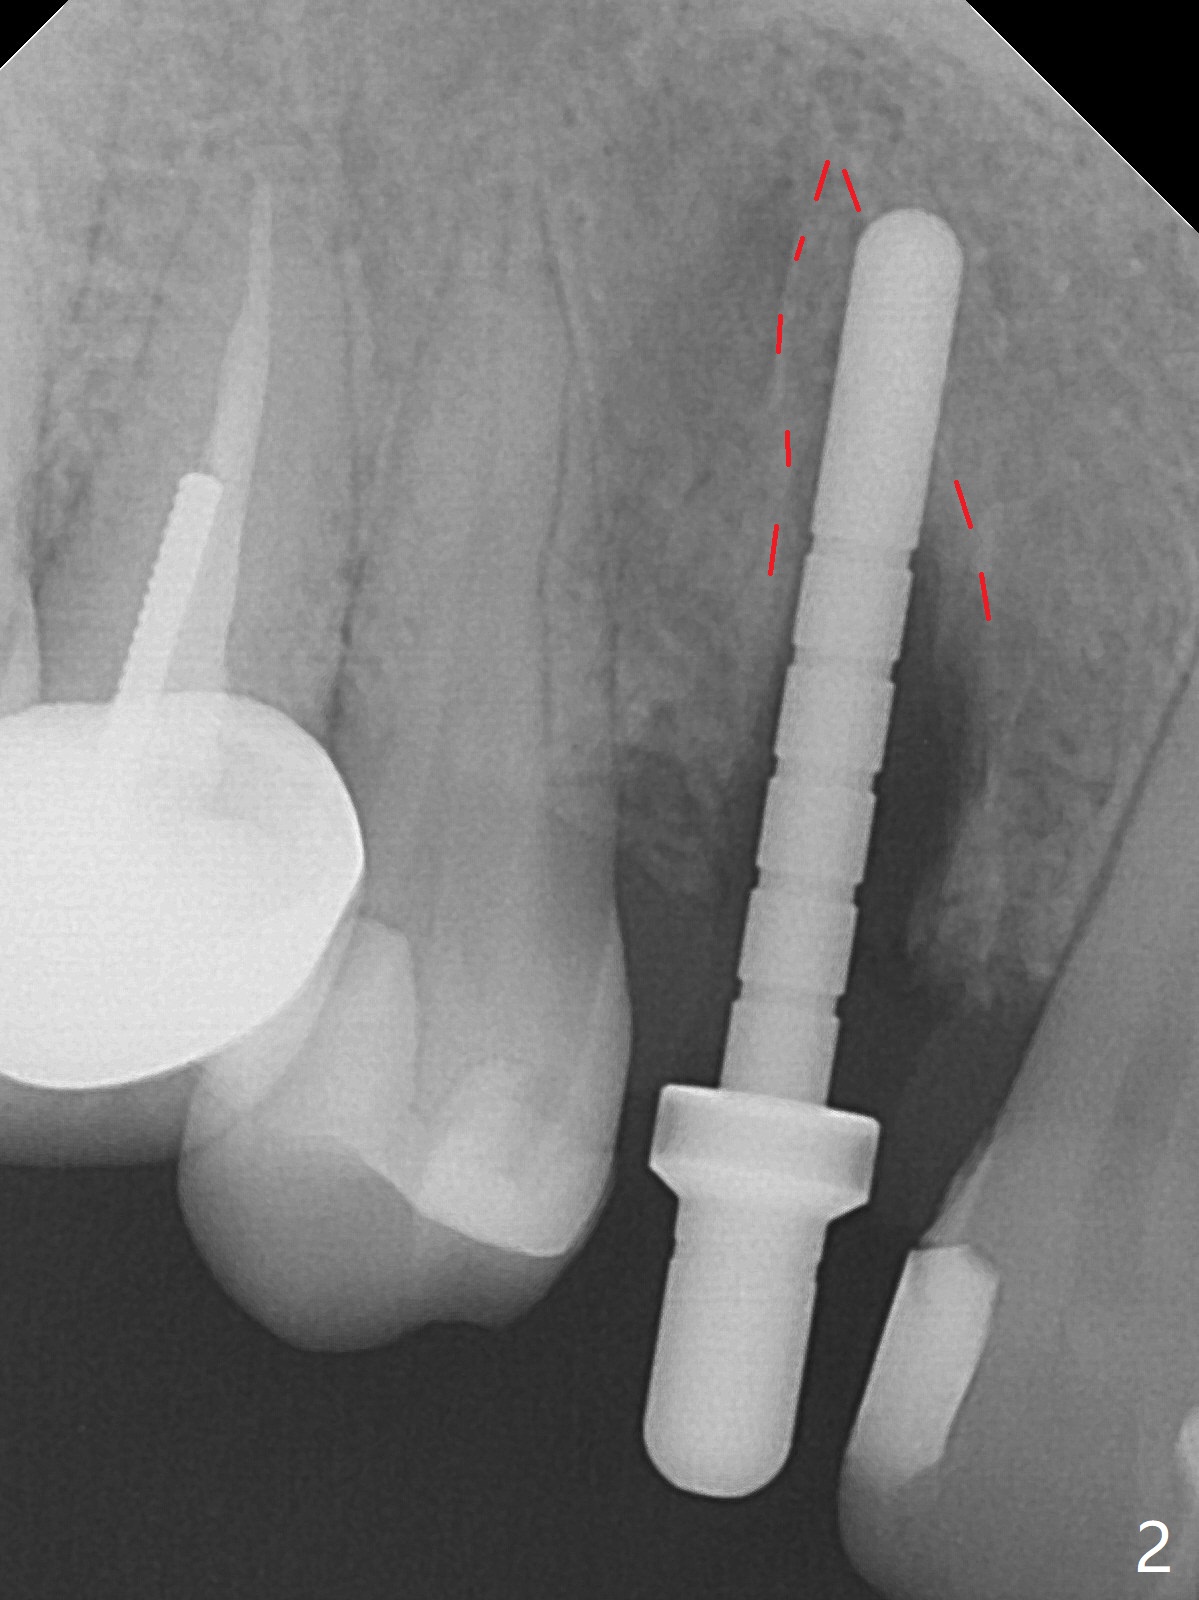

When the tooth #6 with loose crown and post (Fig.1) is extracted, there is no granulation tissue in the socket with the thin intact buccal plate. As planned, osteotomy is initiated in the mesio-palatal slope of the socket (Fig.2 red dashed line). After osteotomy for 3x20 mm (gingival level), a 3.8x15 mm dummy implant is placed partially (Fig.3 D). A final implant with the same dimension is placed with > 50 Ncm (Fig.4). Before and after placement of a 4.5x5(3) mm abutment, Vera graft is placed in the remaining socket space (mainly buccal, Fig.5 *). As routine, an immediate provisional is fabricated with occlusal clearance. The gingiva looks healthy around the provisional 1 week postop (Fig.6 P). Adjust and polish the mesioocclusal composite at #5 if necessary before impression. The bone graft appears to remain in place 4.5 months postop (Fig.7). A bevel buccal subgingival margin is placed prior to impression. The bone density around the coronal portion of the implant increases 9 months postop (4 months post cementation, Fig.8). There is no gingival erythema or edema around the implant crown at #6 ten months post cementation (Fig.6, as compared to preop condition and that of the neighboring crown (*)). Both the buccal and palatal plates are thin or absent 1 year 5 months post cementation (Fig.10,11, as compared to Fig.12 for the tooth #11 (thin buccal bone)). Socket shield should be done with a smaller implant.